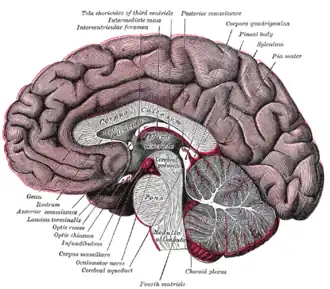

Поперечный разрез среднего мозга на уровне верхнего двухолмия. Срединный сагиттальный разрез головного мозга.

Срединный сагиттальный разрез головного мозга. Проекция желудочков головного мозга на его поверхность